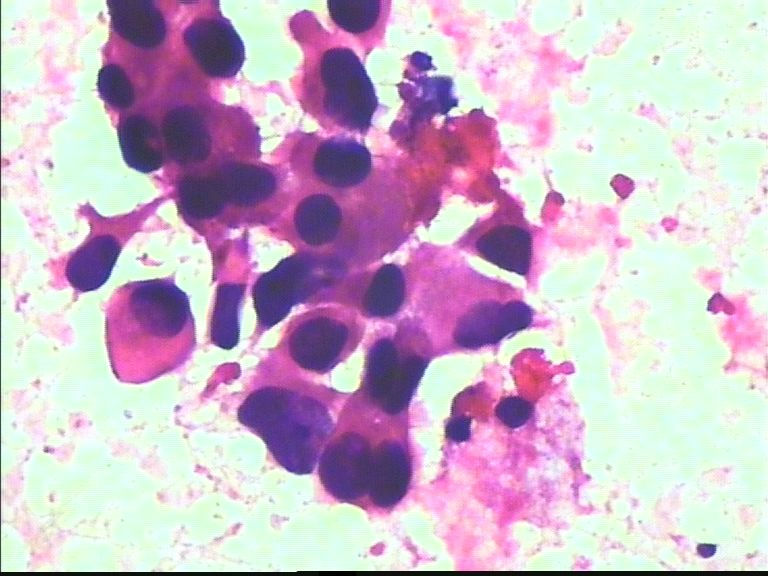

38岁 乳腺肿瘤 女

从所给图看恶性是没什么问题!染色有点过,染色质结构欠清晰;关于细胞学判断浸润的问题我想应综合来判断,如单个细胞的异形性,细胞整体弥散情况,细胞微粒结构以及间质成分等等,个人的认识也起到一定因素,细针穿刺中最常规用的还是--导管癌。

好像重复了。浸润性导管 癌。

浸润导管癌

乳腺癌。

乳腺癌

考虑癌:图18细胞核形式不规则,染色质粗块状,可见核仁.